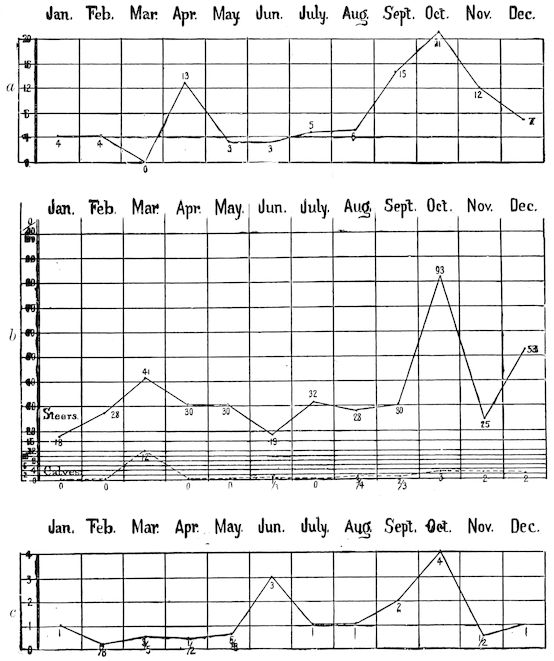

14Course. The development of the disease is slow, lasting from one to three months as a rule, and is little influenced by hygienic conditions. Good milking cows, however, seem to be most frequently attacked, probably because of the great losses of nutritive material which occur through the milk. The calves borne by such animals are often rachitic. Oxen are less commonly attacked. Horses rarely suffer from the disease in France, but frequently in Tonquin. Pigs reared on very poor soil seldom escape attack.

Favouring causes. Whilst conceding that the disease is due to one determining cause, viz. the food, it is unquestionable that other causes may favour its appearance. Abundant milking is one, so that the disease most frequently appears six to eight weeks after calving. Gestation may also determine an attack. The disease is rarer in oxen than in milch cows. Starvation and bad hygienic conditions also have a certain influence; it is well known that during dry years, particularly when fodder is scarce, osseous cachexia makes the greatest ravages. Law states that the disease has been attributed to excess of organic matter in the soil, to succulent watery foods, as rank watery grasses, potatoes, turnips and other roots deficient in nutritious solids. Some agent—microbe or toxin—swallowed with the food has been suspected but not yet isolated.